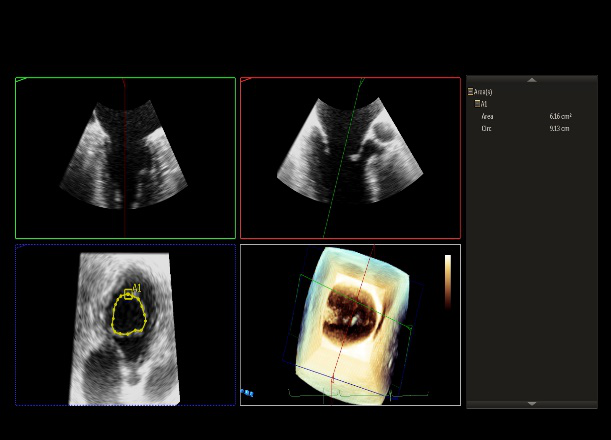

术前超声诊断

LVOT-color:MR(重度),返流面积11.3cm2

肺静脉血流频谱呈收缩期反向

3D-color MV view:血流主要来源于2、3区

Qlab软件勾画估测瓣口面积约:6.16cm2

TEE LVOT切面返流量评估

TEE 4-Ch view返流量评估